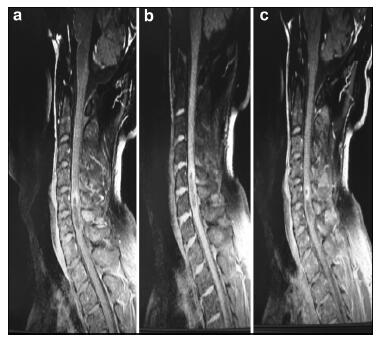

20170512093715  Figure 4 a–c. Postoperative MR images of Case 2.